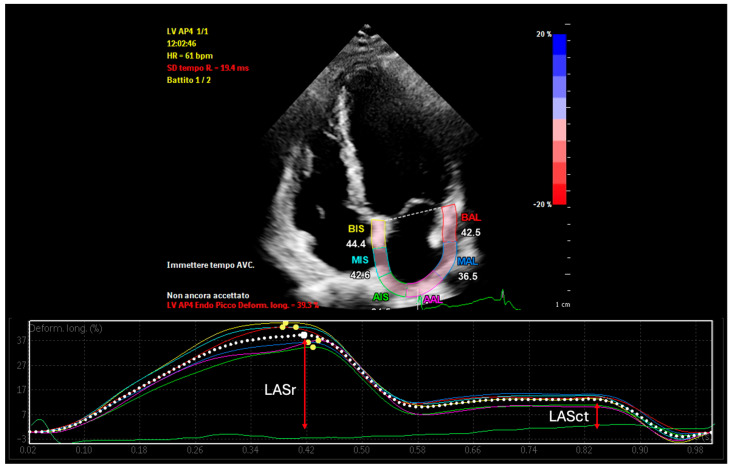

背景:阵发性心房颤动(PAF)是一种常见的心律失常,常采用导管消融治疗,尤其是肺静脉隔离(PVI)。然而,复发仍然很频繁,并且通常与未被识别的左心房结构和功能重塑有关。方法:我们引入超声心动图心房应变和传导评估(EASE)评分作为一种理论的、无创的模型,对导管消融治疗PAF患者的复发风险进行分层。该评分基于综合超声心动图参数能够反映与消融结果相关的心房重构程度的假设。结果:EASE评分结合了六项超声心动图指标——左心房储层应变(LASr)、心房传导时间(PA-TDI)、左心房容积指数(LAVI)、刚度指数(E/ E′/LASr)、E/ E′比和收缩应变(LASct)——每项指标都代表了结构、电或机械重构。总分从0到12分,将患者分为心律失常复发的低、中、高风险三类。初步回顾性数据显示,较高的EASE评分与消融后复发率增加之间存在显著关联。结论:EASE评分为PAF消融的无创风险预测提供了生物学上合理的多维框架。有必要进行前瞻性研究以验证其临床应用并完善其结构。

Background: Paroxysmal atrial fibrillation (PAF) is a common arrhythmia often treated with catheter ablation, particularly pulmonary vein isolation (PVI). However, recurrence remains frequent and is often linked to unrecognized structural and functional remodeling of the left atrium. Methods: We introduce the Echocardiographic Atrial Strain and conduction Evaluation (EASE) score as a theoretical, noninvasive model to stratify recurrence risk in patients undergoing catheter ablation for PAF. The score is based on the hypothesis that integrated echocardiographic parameters can reflect the extent of atrial remodeling relevant to ablation outcomes. Results: The EASE score combines six echocardiographic metrics-left atrial reservoir strain (LASr), atrial conduction time (PA-TDI), left atrial volume index (LAVI), stiffness index (E/e'/LASr), E/e' ratio, and contractile strain (LASct)-each representing structural, electrical, or mechanical remodeling. The total score ranges from 0 to 12, stratifying patients into low, intermediate, and high-risk categories for arrhythmia recurrence. Preliminary retrospective data suggest a significant association between higher EASE scores and increased recurrence rates following ablation. Conclusions: The EASE score offers a biologically plausible, multidimensional framework for noninvasive risk prediction in PAF ablation. Prospective studies are warranted to validate its clinical utility and refine its structure.